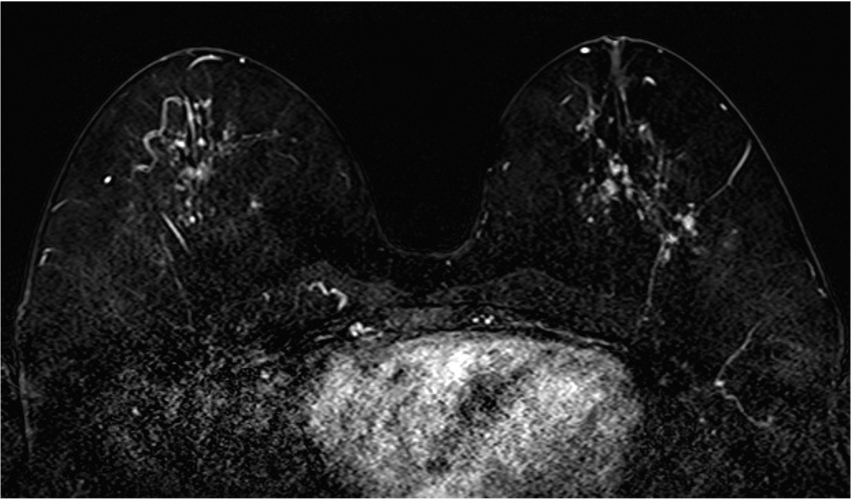

5. Ultrafast DCE

超早期相では、DCISの病変(矢印)は、超早期(8相目: 造影剤注入25.7秒後)から急速に造影され、BPEの影響を受けることなく病変を認識することができる。DCISの病変は、区域性の分布を示しているが、乳頭下には腫瘍の進展を疑うような造影域は認めない。